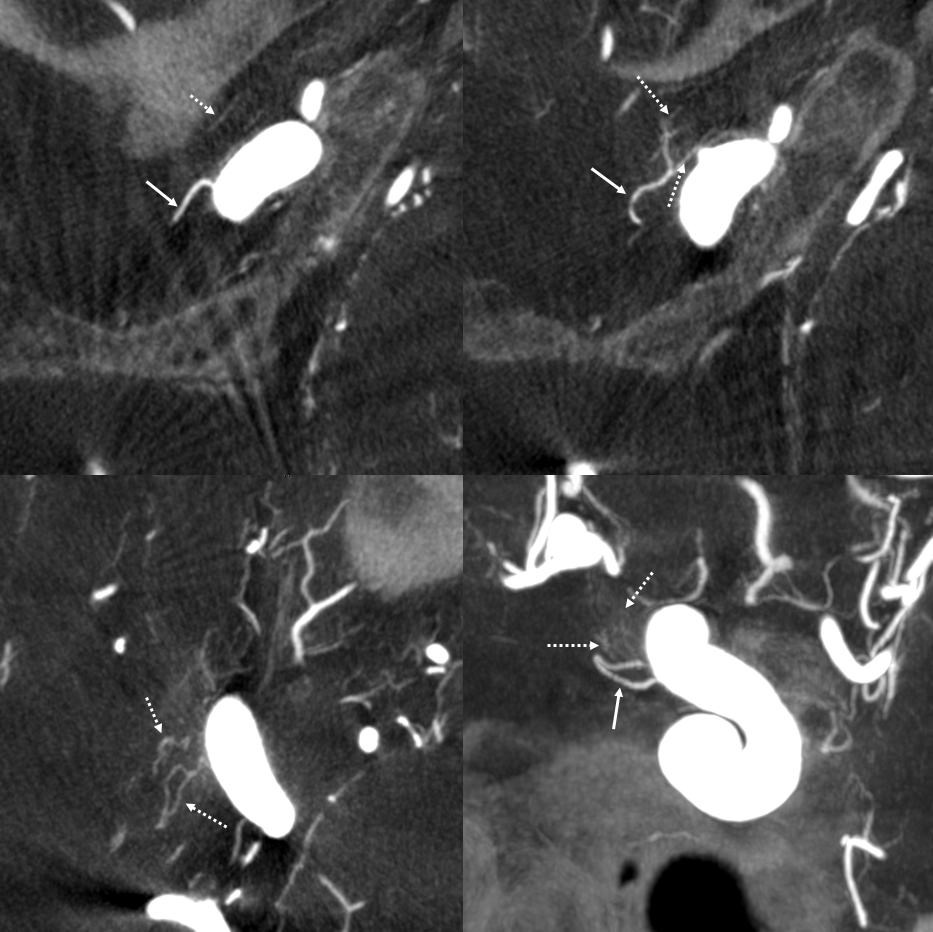

What supplies the bulk of optic nerve? Central Retinal artery is for the distal portion of nerve and retina. What about the rest — intracranial, intracanalicular, proximal intraconal segments? The answer is not clear (let me know if you do), but i believe the bulk of it comes from the superior hypophyseals. It is probably in balance with the recurrent branch of the central retinal artery. Below is an example of an especially prominent proximal-most superior hypophyseal (arrows) supplying the pituitary stalks and optic nerve in the canalicular and intracranial locations. Note how well one can see the branch in coronal view (bottom left image). In this case there are two large superior hypophyseals — the more distal one (dashed arrows) supplies predominantly the pituitary stalk. The inferior hypophyseal artery is marked by arrowhead. Lower right image is coronal.

Movie is the best way

Here too superior hypophyseal (arrow) supply of the intracranial optic nerve (oval) and possibly chiasm is shown definitively (lower right image is coronal)

No annotations

Best seen in this movie (pause to scroll)

VR — the anterior-most branch of the superior hypophyseals is usually the largest (arrow). The others are too small to see on a VR image

MIPS. The anterior, proximal-most branch (arrow) tends to supply the optic nerve (white oval), while the more posterior branches (dashed arrows), when present, supply more posterior structures such as chiasm and tract (dashed oval)

A highly unusual branch originating from ILT region swings underneath the cavernous ICA and supplies the floor of the pituitary fossa. Yet unknown, as far as i know

More Optic Nerve Supply — its easier to see on MIPS, but with the right windowing, and stereo, VR imaging is also possible. Here, there are 3 superior hypophyseals seen. The anterior-most (arrow) is usually the largest, suppling the optic nerve (dashed arrow) and chiasm (ball arrow). The middle and posterior hypophyseals (arrowheads) supply the stalk.

Stereo of VR image. Same arrows. The stalk is open arrow.

Another patient — also 3 arteries. Cave origin of the anterior-most (arrows) one. The middle one (arrowheads) also supplies the optic nerve. The posterior one (dashed arrows) is for the stalk.

VR images (stereo pair on bottom). The cave origin of the anterior branch is most beautifully seen in the upper right image.